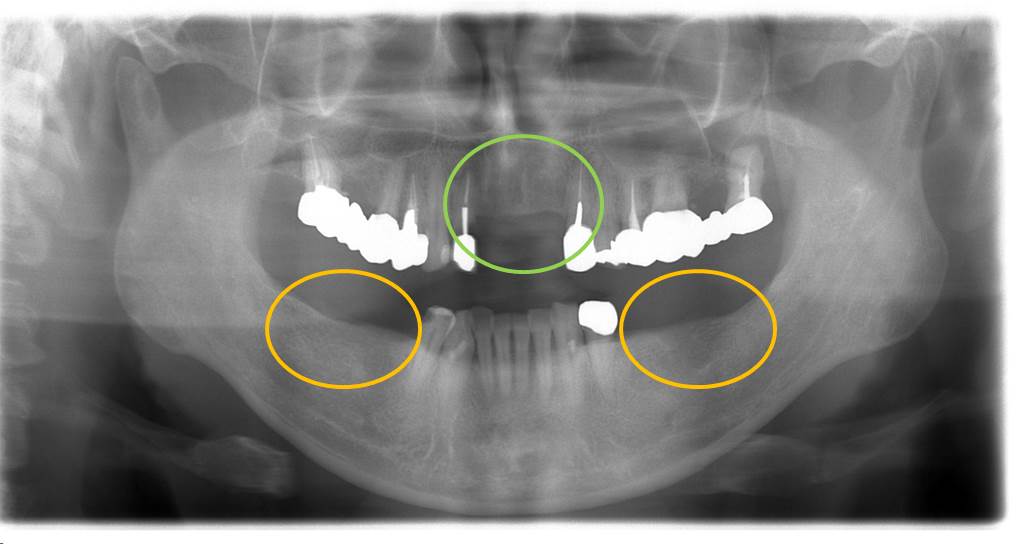

X線写真です。

インプラント埋入直後の写真です。

術前のレントゲン写真です。

緑○部分とオレンジ○部分が欠損しています。

緑○部分は歯を切削してブリッジを予定し、オレンジ○部分はインプラントとする計画としました。